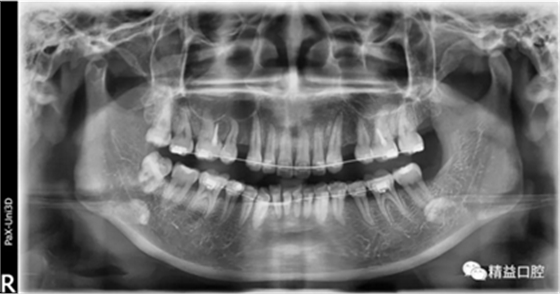

矯正前全口曲斷片

從片子上可以清除看到,上牙門牙牙根吸收非常厲害。